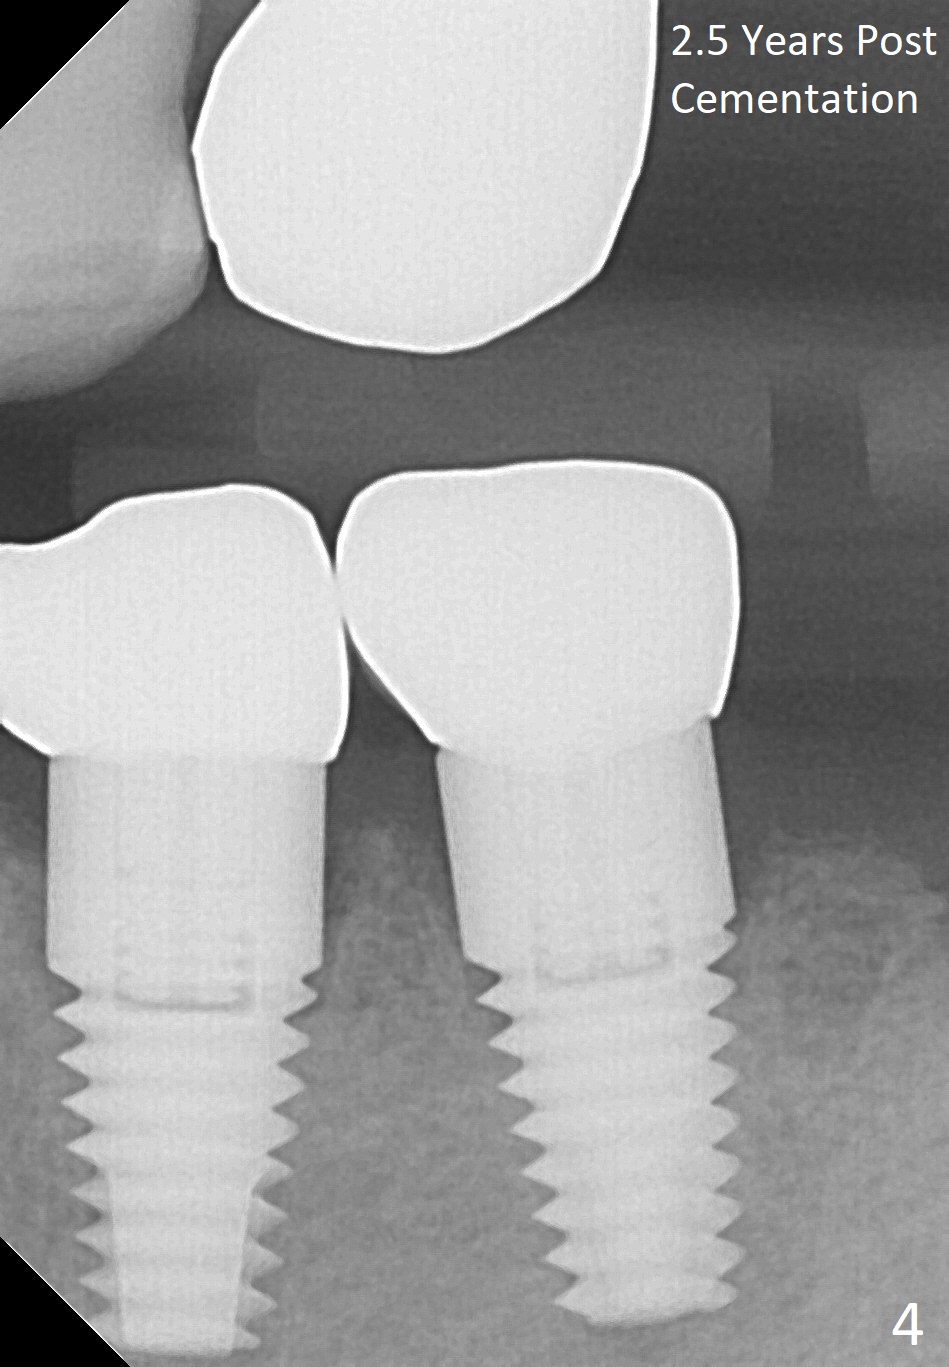

Two implants are to be placed at the sites of #20 and 21 (Fig.1 CT sagittal section) to be used as ortho anchorages. When paralleling pins (Fig.2 P) are inserted, they happen to be in the original sockets (arrowheads). Two 4.5x11 mm implants are also placed more or less in the original sockets (Fig.3). Postop X-ray is shown. Two separate provisional crowns are to be fabricated with the occlusal table of #20 being lower, since #13 has mobility and has supraerupted. Leave a space (1-2 mm) mesial to #21 provisional so that the tooth #22 and 23 can be moved distally. A premolar band is going to be placed at #21. There is no bone loss 2.5 years (Fig.4) or 3 years 9 months (Fig.5,6 CT) post cementation. Return to Implant & Ortho Full Mouth Reconstruction 3 24/26 28 30 Xin Wei, DDS, PhD, MS 1st edition 10/04/2014, last revision 12/16/2018